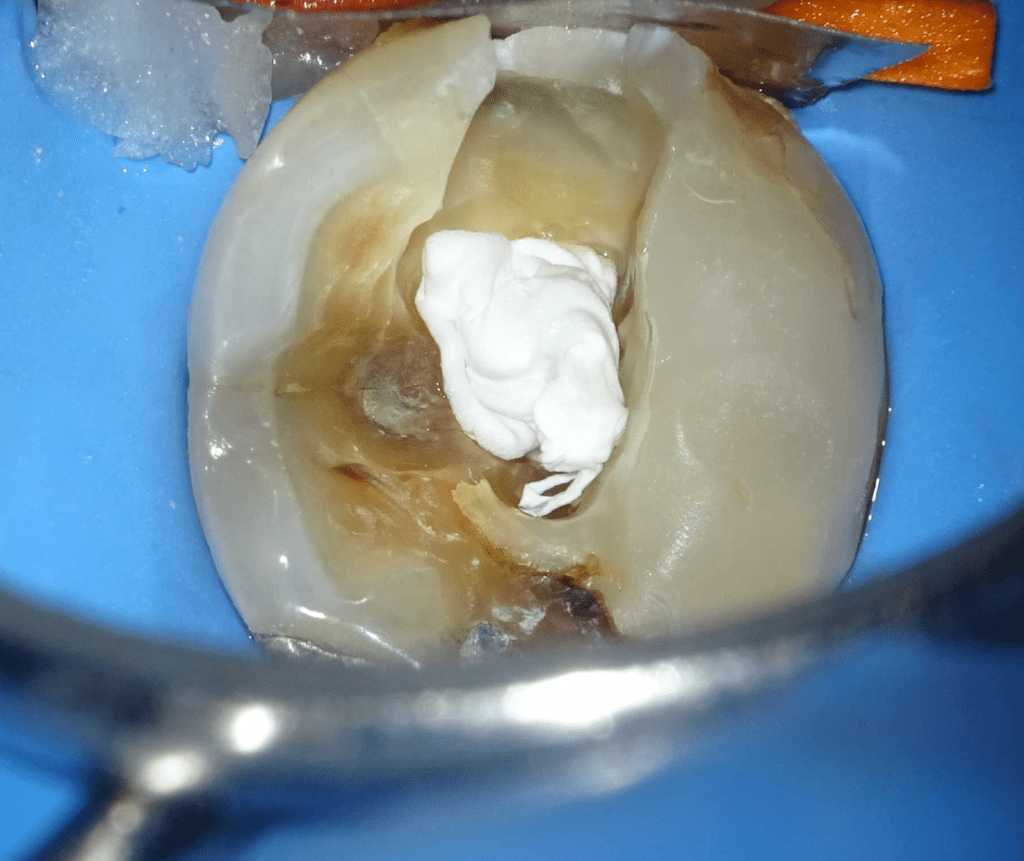

Pulpotomía biodentine + reco preendio